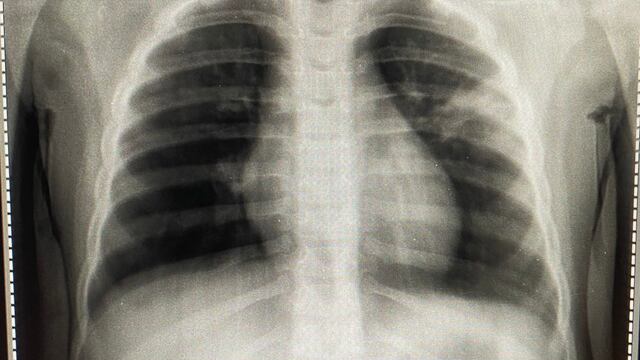

Pediatra mostró la radiografía de los pulmones dañados de un niño

El pasado 28 de agosto un doctor especializado en pediatría mostró en sus redes sociales una radiografía de unos pulmones.

En ella se puede apreciar al órgano visiblemente dañado; pues presentan inflamación, mejor conocida como fibrosis.

Sin embargo, lo que más sorprendió a los internautas de la publicación fue que el pediatra indicó que se trataba de los pulmones de un bebé de dos años, quien fue contagiado de Covid-19.

“Empezó con diarrea luego fiebre…motivo de consulta tos y saturación en casa de 76%… ah y tiene 2 años de vida y es aparentemente previa sana. ¿Usted qué cree que sea?”